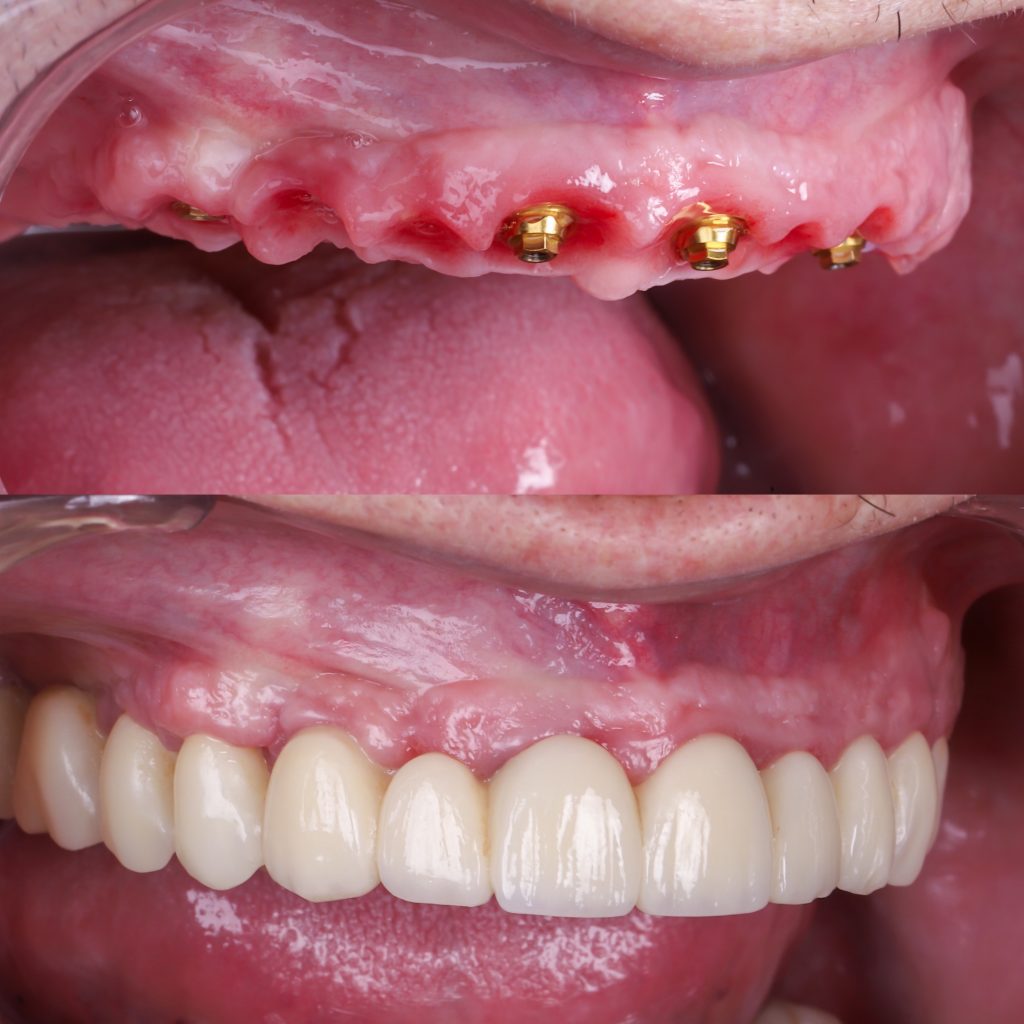

Permiten colocar dientes fijos en 24 horas mediante la técnica carga inmediata.

Estética inmediata gracias a la prótesis provisional realizada por nuestro laboratorio en exclusiva.

Antes y después